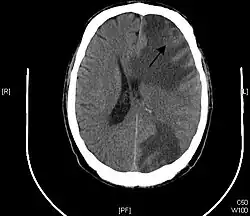

Brain - CT scan - Metastatic Pulmonary Adenocarcinoma. Arrow points to extensive edema of frontal lobe due to 23mm mass. Second area of edema can be seen in the left parietal-occipital region. - Genitourinary tract cancers, 11%